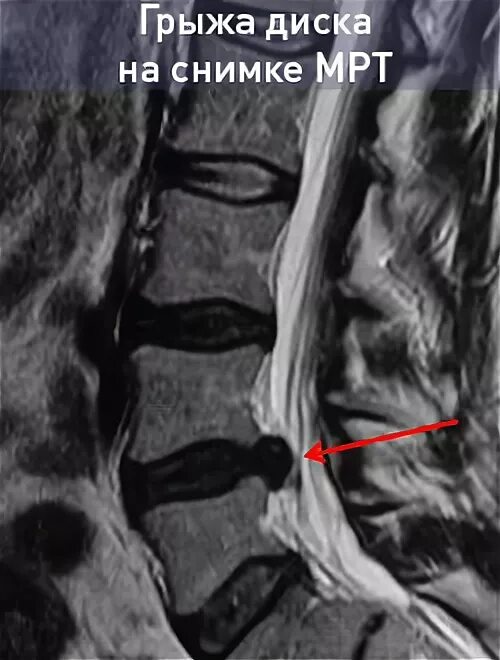

Грыжа диска мрт